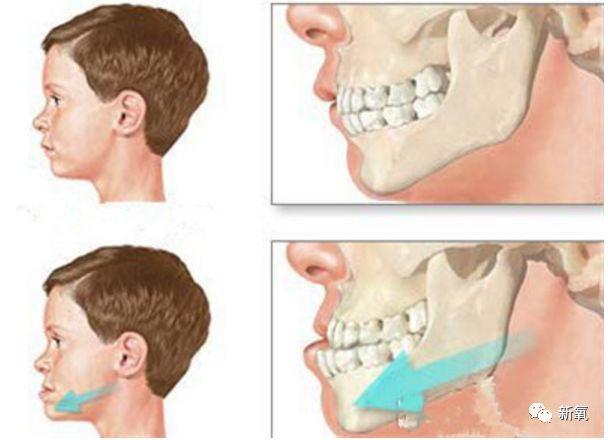

看下面的骨骼图,左侧是地包天,右侧是正常颌的。可以很明显的看见左侧下颌发育过度,上颌发育不足。

也就是说,别的牙齿问题只是影响自己,而地包天如果放置不管,它还影响其他骨头。成人后就极有可能是这个状态。

限制上颌骨的发育,进而影响眼底的眶骨乃至整个中面部的发育,于是乎···

可是如果在面部各处还在发育的时候就进行干预,牙齿、骨骼的改建能力极强,一些颌骨发育问题就可以被改善。最终实现不动骨改变颌面骨骼的目的。

看下面这个真人案例,仅在整牙的矫正下,不仅下牙列回到正常的位置,连原本被限制发育、显得凹陷的中面部也变得正常,明显侧脸变得饱满了。

如果错过这个时期,骨骼全部定型后想要矫正这个问题,就只能动骨了···

而且仅将下颌骨推进去也无法让上颌再长出来,也就意味着:之后还需要将受到影响发育不足的鼻基底、鼻子补起来。(注意看右边的鼻基底和上颌依然是扁平的)

同样的道理,深覆盖、深覆合、龅牙嘴凸这些上颌过度发育的情况,也会明显影响下颌骨的发育。

所以我们常见的嘴凸、龅牙的例子,几乎都伴有下巴后缩、下颌短小等下颌骨发育不足的情况。

和地包天是一样的原理,在骨骼成型前,将其用外力引导到正确位置。利用牙槽骨的改建能力,让颌骨发育问题得到改善。

如果是比较严重的凸嘴,成年后就只能选择动骨(正颌)手术来解决这个问题了额··· 如果有下巴严重后缩的,还需要下颌的处理或隆下巴。